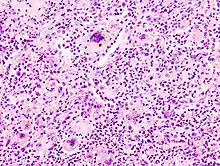

Aspiration pneumonia is typically diagnosed by a combination of clinical circumstances (people with risk factors for aspiration) and radiologic findings (an infiltrate in the proper location).[2] A chest x-ray is typically performed in cases where any pneumonia is suspected, including aspiration pneumonia.[17] Findings on chest x-ray supportive of aspiration pneumonia include localized consolidation depending on the patient's position when the aspiration occurred.[18] For example, people that are supine when they aspirate often develop consolidation in the right lower lobe of the lung.[18] Sputum cultures are not used for diagnosing aspiration pneumonia because of the high risk of contamination.[19] Clinical symptoms may also increase suspicion of aspiration pneumonia, including new difficulty breathing and fever after an aspiration event.[6] Likewise, physical exam findings such as altered breath sounds heard in the affected lung fields may also be suggestive of aspiration pneumonia.[6] Some cases of aspiration pneumonia are caused by aspiration of food particles or other particulate substances like pill fragments; these can be diagnosed by pathologists on lung biopsy specimens.[20]